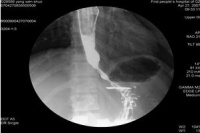

1.钡餐检查 钡餐常难以通过贲门部而潴留于食管下端,并显示为1~3cm长的、

贲门失弛缓症

对称的、粘膜纹政党的漏斗形狭窄,其上段食管呈现不同程度的扩张、处长与弯曲,无蠕动波。如予热饮,舌下含服硝酸甘油片或吸入亚硝酸异戊酯,每见食管贲门弛缓;如予冷饮,则使贲门更难以松弛。潴留的食物残渣可在钡餐造影时呈现充盈缺损,故检查前应作食管引流与灌洗。